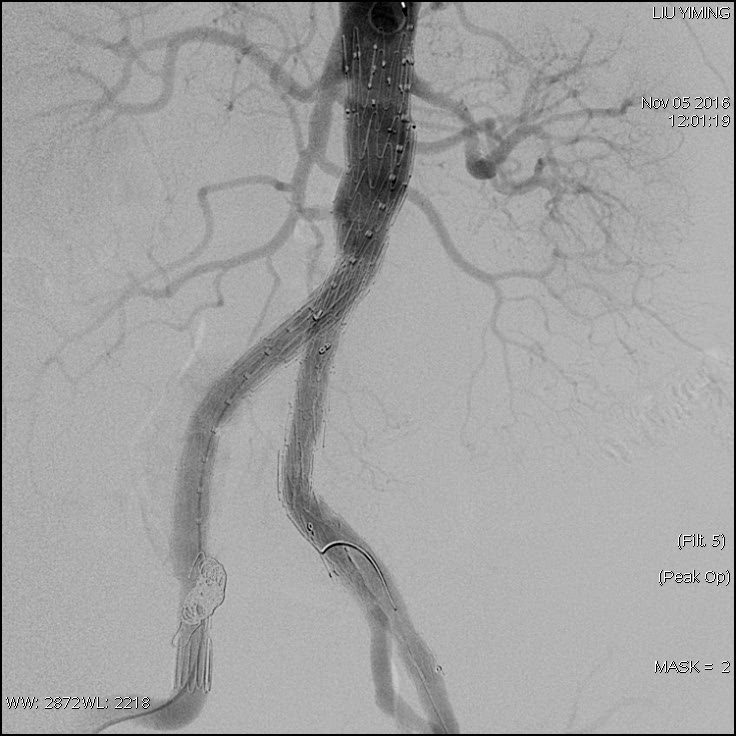

其中,在复杂主动脉病变腔内修复术应用手术直播中,郭伟教授带领其团队使用先健科技公司的髂动脉分叉支架系统(IBD)以完全腔内重建的方式成功修复复杂腹主动脉瘤及髂动脉瘤。该例手术患者为64岁的男性,被诊断为肾下腹主动脉瘤,瘤体最大直径约6.5cm,双侧髂动脉瘤。患者成功植入先健科技IBD支架,定位准确,无内漏,成功保留了左侧髂内动脉,术后造影显示髂内动脉通畅。

图:术前造影、术中造影、术后造影

郭伟教授团队手术所使用的髂动脉分叉支架系统(IBD)由先健科技公司自主研发,是目前国内唯一一款髂动脉分叉支架,目前正在国内进行上市前多中心临床试验。该支架系统由髂分叉支架和髂内覆膜支架组成。髂分叉分为长短主体两个系列,支架采用后释放,释放力小。短分支采用独特的非等高波形设计,导丝进入方便,支架定位准确,更容易判断方位。髂内覆膜支架可采用肱动脉入路或对侧翻山方法置入,使用方便灵活,其与髂分叉对接时定位准确,二者连接牢固。该产品在上市后将成为髂动脉瘤患者保留髂内动脉的最佳治疗选择。